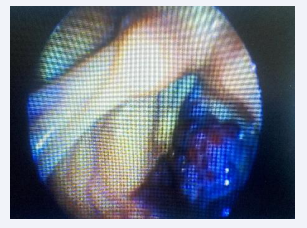

Nasopharyngolaryngeal fibroscopy revealed a multiple or single (to be clarified) tumor-like lesion with a vascular appearance and bluish coloration, non-pulsatile, and extensive. It occupied a significant volume in the supraglottic and left glottic region, at the level of Areas d’Avila I and II (Figures 1-3) [16,17].

Videolaryngoscopy capture image demonstrating laryngeal  hemangioma

Figure 1: Videolaryngoscopy capture image demonstrating laryngeal hemangioma

Videolaryngoscopy capture image demonstrating laryngeal  hemangioma with supraglottic extension

Figure 2 Videolaryngoscopy capture image demonstrating laryngeal hemangioma with supraglottic extension